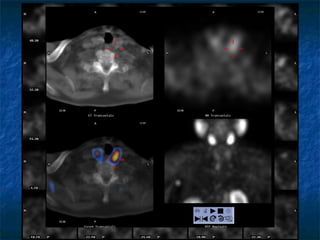

I-123 10 mCi SPECT coronal

Λεμθαδέκαξ? Καηαθνάηεζε ζηέιμο ζημκ μηζμθάγμ Οηζοθάγος Οηζοθάγος